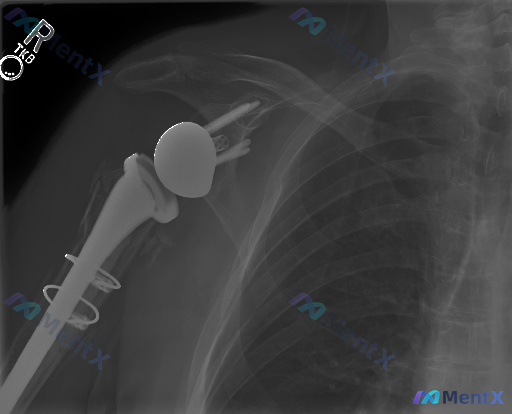

这张肩关节X光片的“异常”,你能分清是手术改变还是并发症吗?

整理到一张很有意思的术后影像读片材料——一张右侧肩关节正位X光片。

第一眼看到“异常”很明显,但最关键的是:哪些是术后预期的改变?哪些是真正需要警惕的病理异常?

- 可见“反置”的关节结构:关节盂侧是金属球体,肱骨侧是凹面杯

- 肱骨近端有假体柄,还有多道环扎钢丝

- 关节盂基座有螺钉固定

- 目前骨-假体界面看起来清晰,没有明显的进行性透亮线